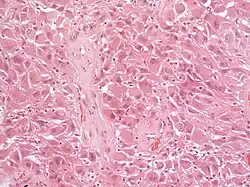

Histologisch sind für den Tumor astrozytäre Riesenzellen charakteristisch; die Morphologie der Tumorzellen kann jedoch von polygonalen Zellen mit glasigem Zytoplasma und ganglioiden Kernen bis hin zu spindelförmigen Zellen in einer fibrillären Matrix reichen. Die Tumorzellen zeigen eine variable Expression von GFAP, S-100, Synaptophysin und Neurofilament.